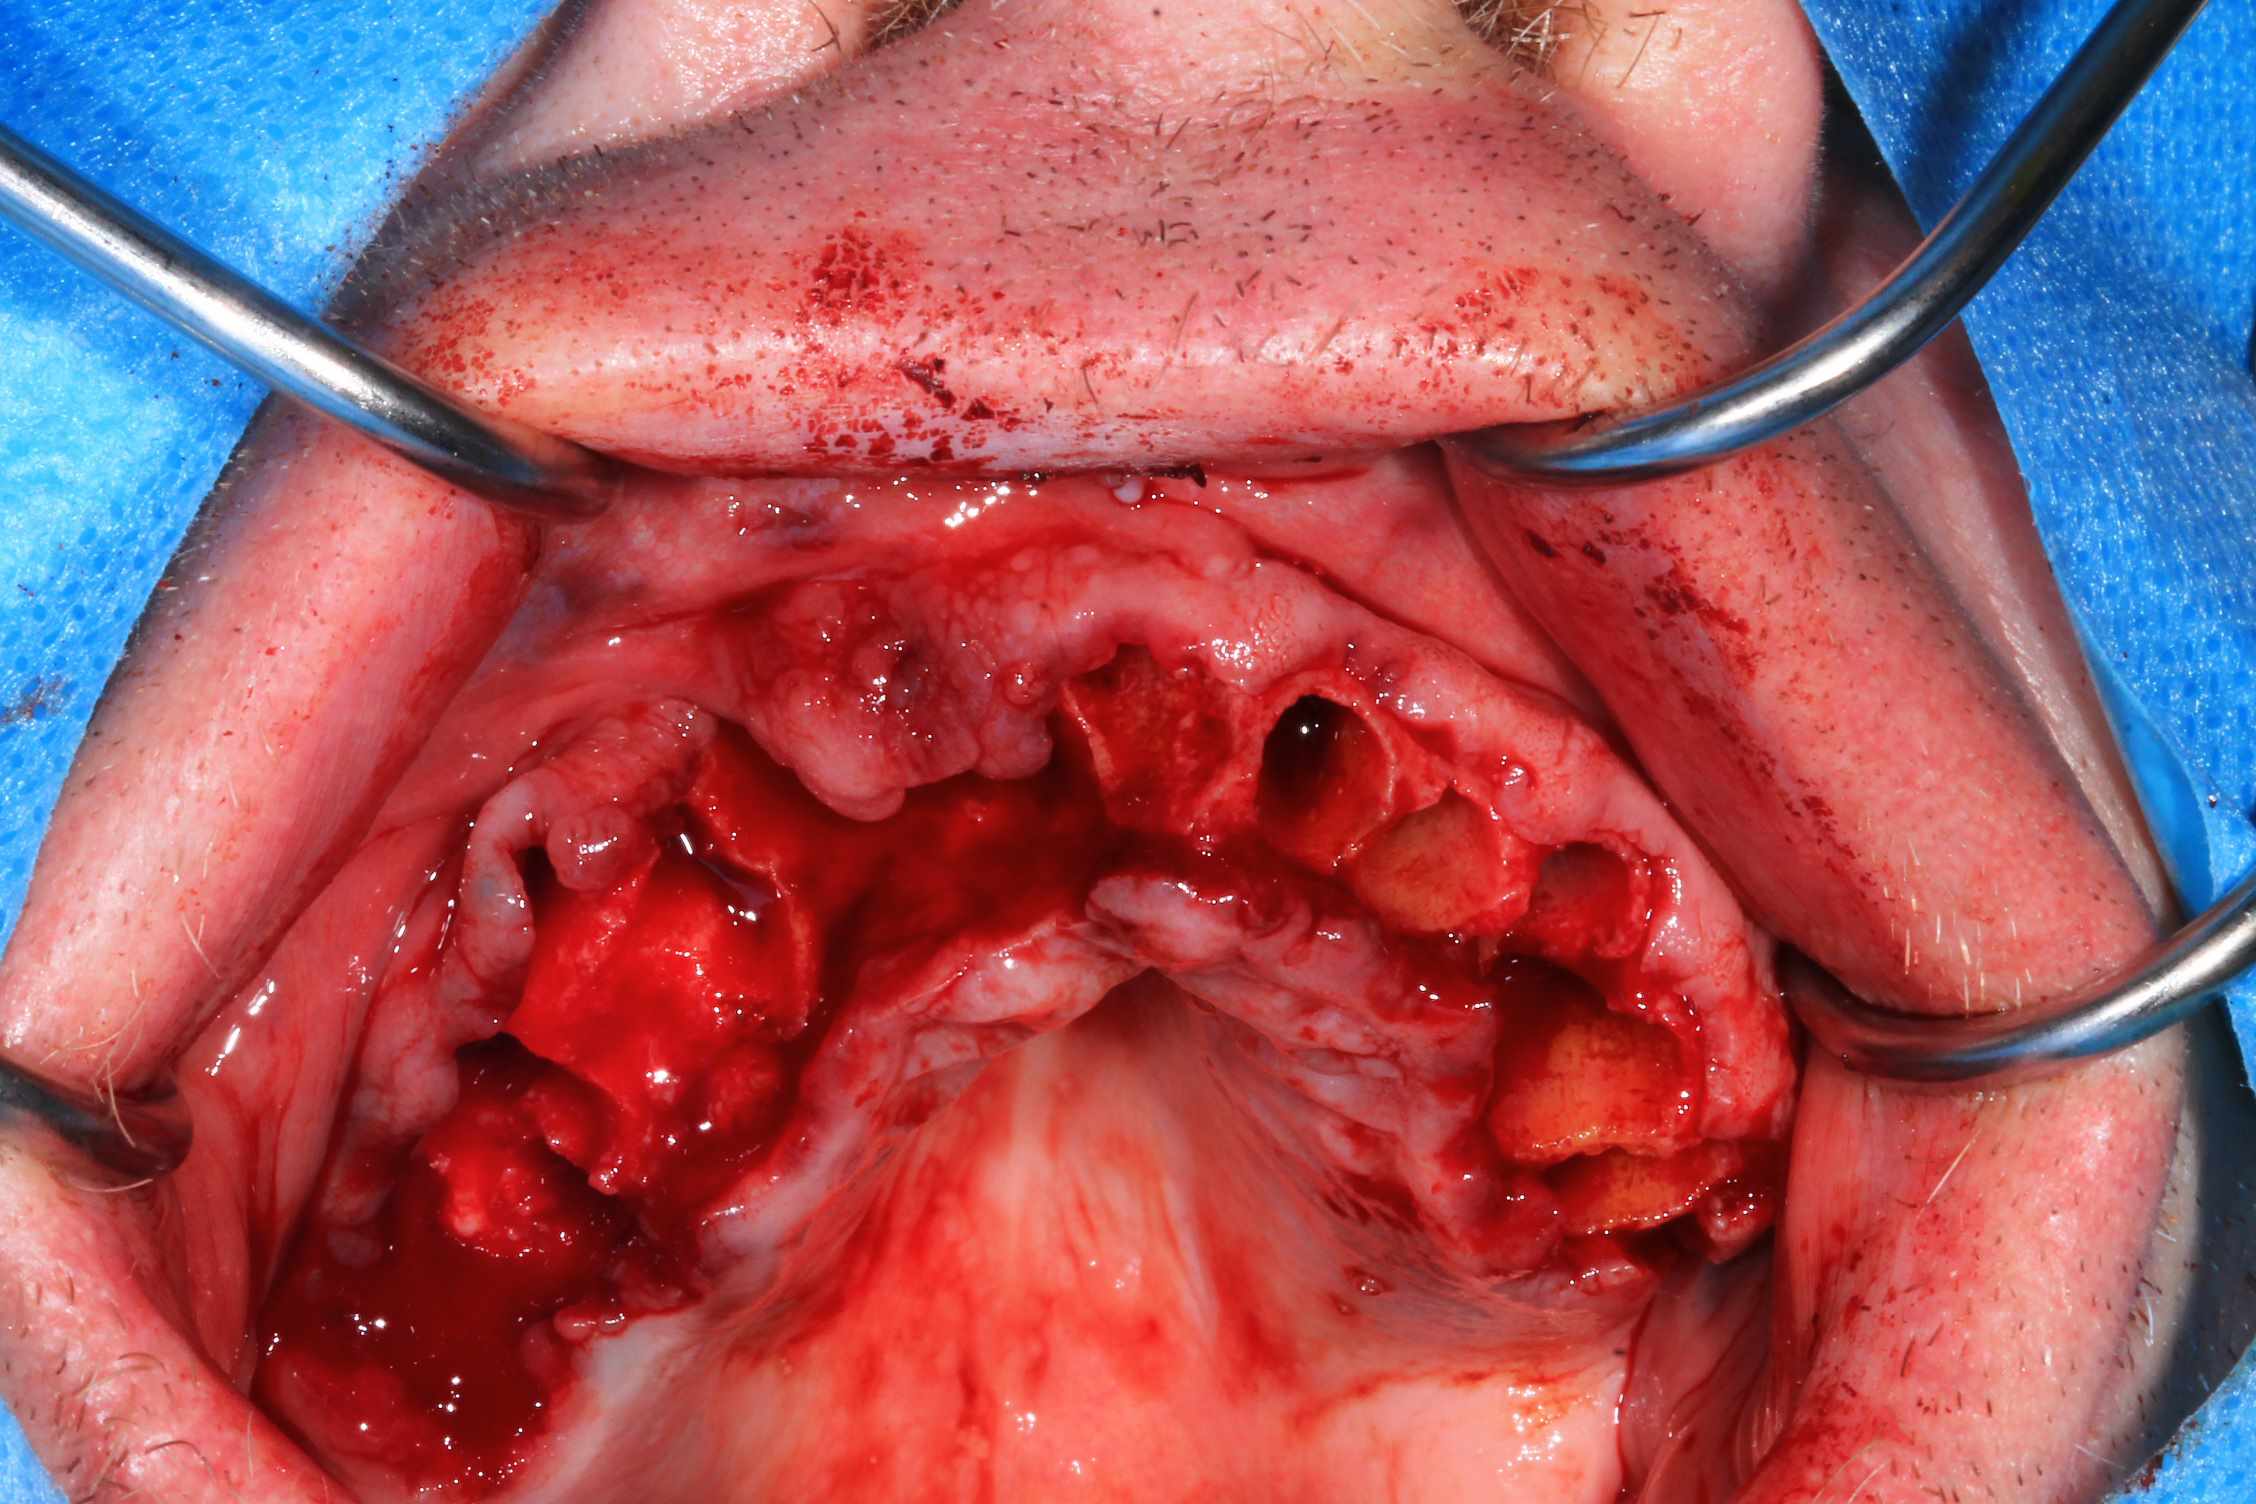

Cas 2 , suite : avec une saussage au passage..

le patient arrive a 9 h, Prise de sang, PRF, injection de corticoïde, anesthésie et installation au bloc. Premier coup de bistouri a 9h30. Dernière suture a 11h30.